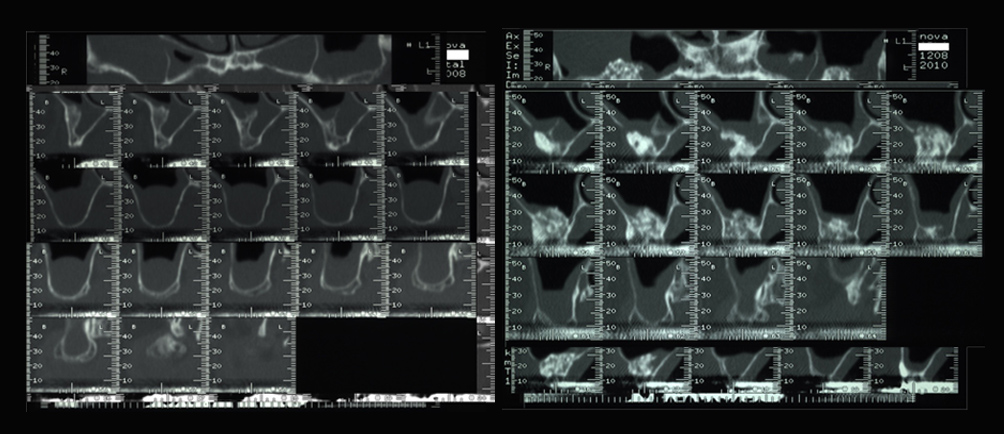

Rigenerazione ossea del pavimento del seno mascellare con incremento verticale di 12 mm ed orizzontale di 10 mm

Risultati estetici e funzionali conseguiti con la CHIRURGIA RIGENERATIVA